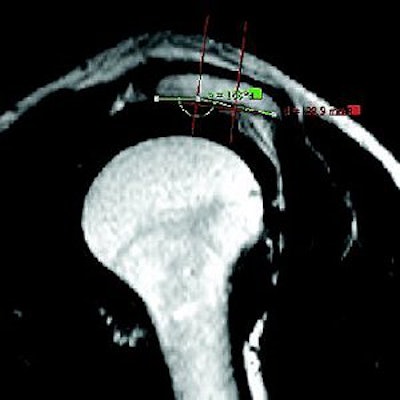

![]() ![]() ![]() |

| A 63-year-old man with impingement syndrome of shoulder. Whereas outlet view radiograph (top) depicts curved acromion (type 2), MR image (middle) in position S-1 reveals blunt acromial hook (type 3), which is also confirmed by 3D model (above) and intraoperatively. Mayerhoefer ME, Breitenseher MJ, Roposch A, Treitl C, Wurnig C, "Comparison of MRI and Conventional Radiography for Assessment of Acromial Shape" (AJR 2005; 184:671-675). |